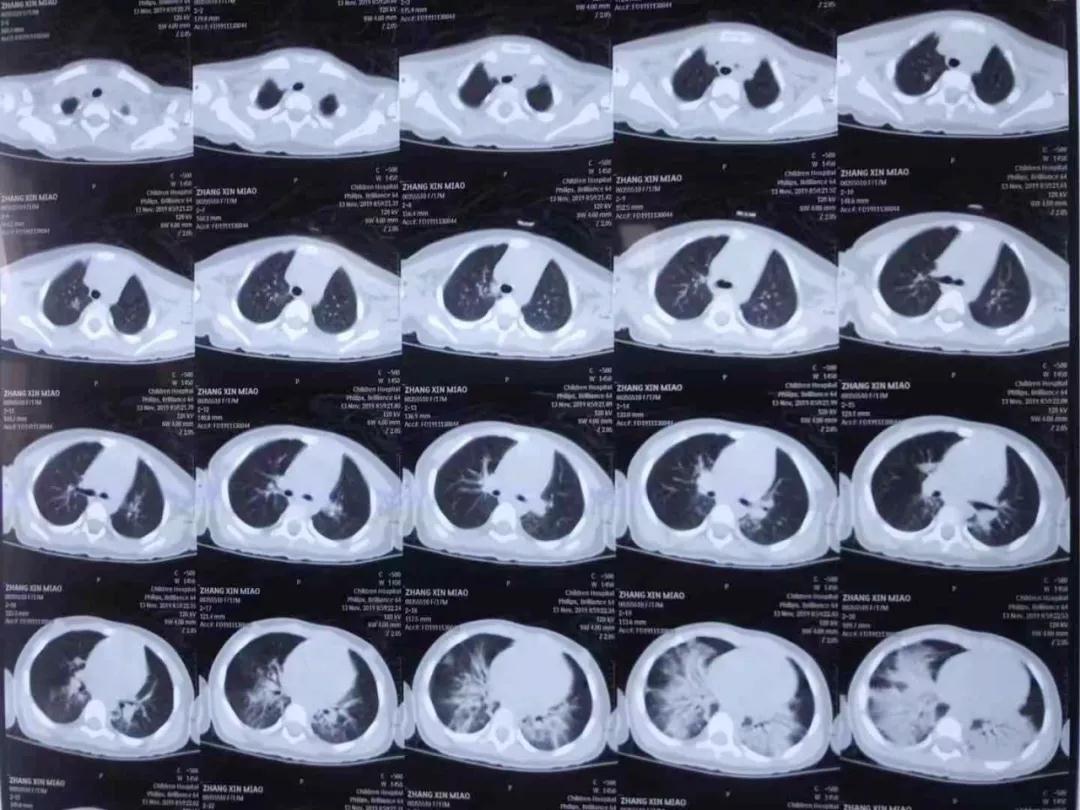

德州扑克游戏网 PICU主任单立业说,苗苗来院时呼吸困难、意识淡薄直接进入重症监护室,经检查是洗衣有机溶剂中毒,造成急性肺水肿、急性肺损伤以及心肌损害,随即给予无创呼吸机通气,抗炎、保护脏器功能等综合治疗。

转危为安

5天120个小时,专家协同会诊、抢救、稳定患儿生命体征直至脱离生命危险,在重症监护病房治疗一周后,苗苗身体各项指标好转,撤掉呼吸机,转到普通病房,11月26日早上,苗苗出院回家。